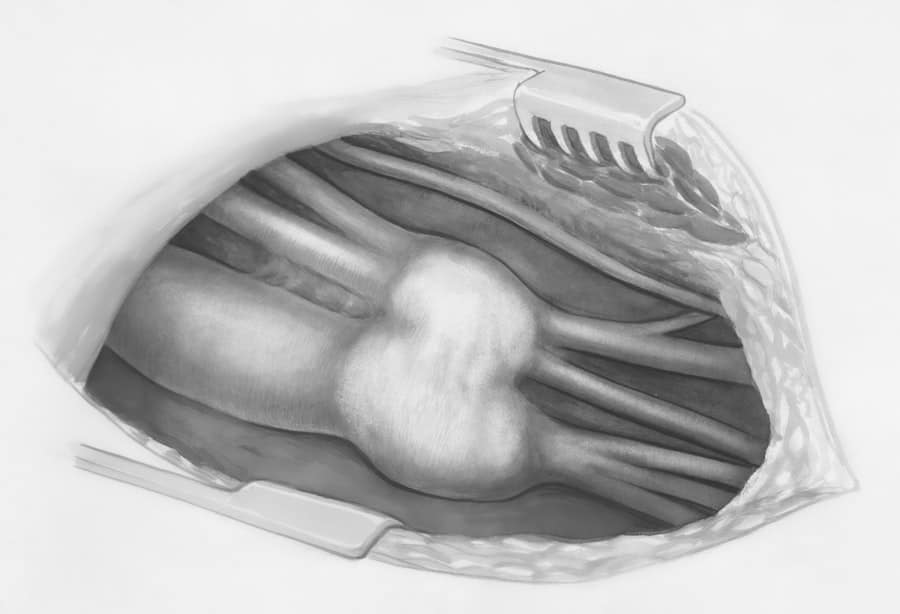

Surgical Techniques Employed

While the specific techniques used will vary based on your anatomy and goals, the underlying principle remains consistent: subtlety and precision.

Open vs. Closed Rhinoplasty

- Open Rhinoplasty: This technique involves a small external incision at the base of the columella (the strip of skin between your nostrils). This allows the surgeon direct visibility to the nasal structures, enabling precise modifications. It’s often favored for more complex revisions or when significant tip work is required to achieve natural-looking contours.

- Closed Rhinoplasty: In this approach, all incisions are made internally within the nostrils. This method leaves no visible external scarring but can offer less direct visualization for the surgeon, depending on the complexity of the case. It’s often suitable for less extensive tip adjustments or minor dorsal hump reductions.

Cartilage Grafts

When augmentation or support is needed, particularly for the tip, cartilage grafts are frequently used.

Septal Cartilage

This is the most common source, harvested from your own nasal septum. It’s readily available and easy to sculpt.

Ear Cartilage

If more graft material is needed, or if septal cartilage is insufficient, cartilage from your ear can be used. It’s slightly more curved but still provides good structural support.

Rib Cartilage

In cases requiring significant structural alteration or for revision rhinoplasty, rib cartilage may be utilized. It’s the strongest and most abundant option, but its use can sometimes lead to slight warping over time and may be perceived as less “natural” due to its bulk.

Suturing and Structural Support

Strategic placement of sutures and grafts is essential to create the desired shape and maintain structural integrity for long-term natural results.